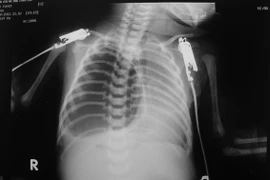

Báo động tình trạng hóc dị vật ở trẻ em

ANTĐ - Trong vòng nửa tháng trở lại đây, tại Hà Nội và TP.HCM đã tiếp nhận và cấp cứu nhiều trường hợp hóc dị vật ở trẻ nhỏ. Đáng báo động, những trường hợp này đều là các bé nhỏ, hóc phải những dị vật nguy hiểm, ảnh hưởng đến tính mạng.